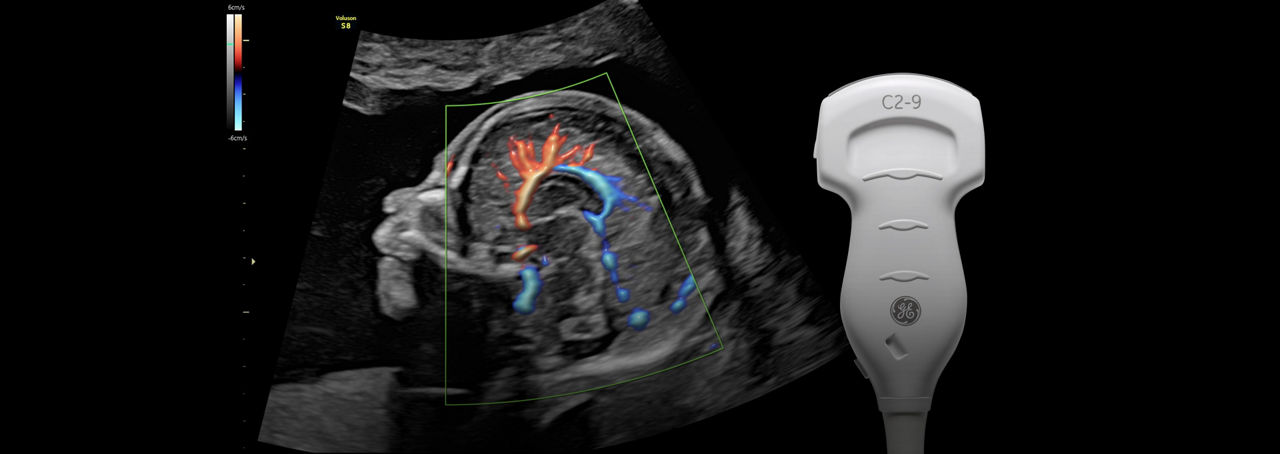

Exceptional Color Sensitivity

Enhance visualization of small vessels and borders of the fetal heart with Radiantflow™; powering greater color sensitivity for a more dynamic 3D-like appearance.